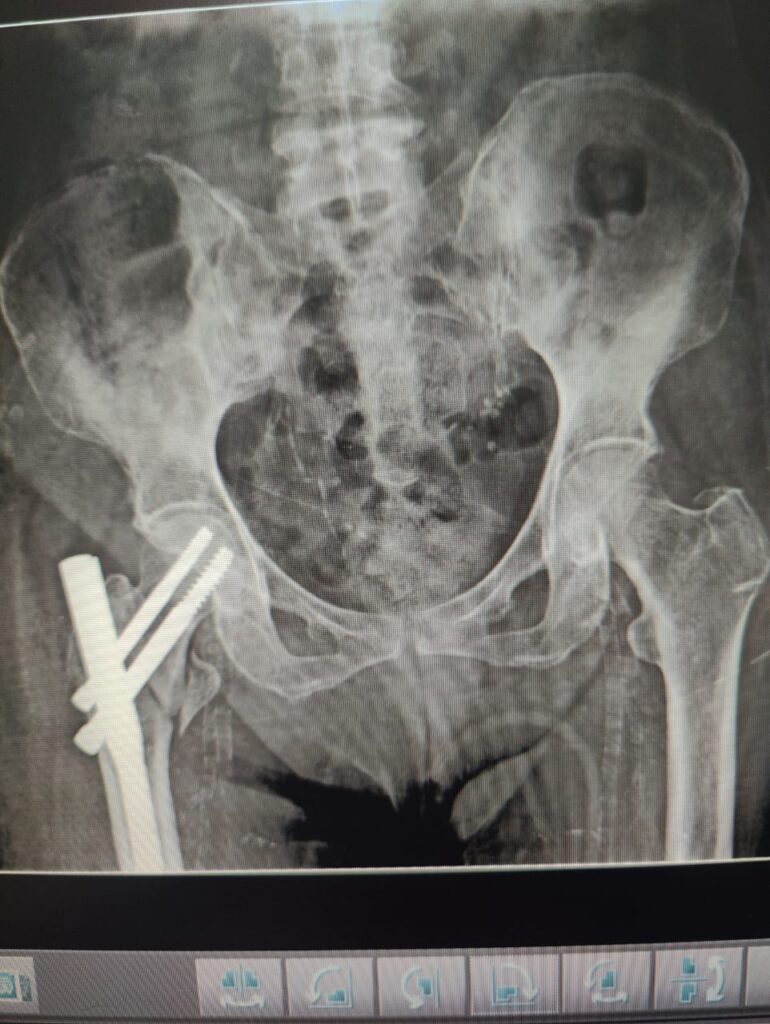

- PFN (Proximal Femoral Nail)

A metal rod is inserted into the thigh bone to stabilize the fracture.

Best suited for intertrochanteric and subtrochanteric fractures.

Strong and allows early movement. - DHS (Dynamic Hip Screw)